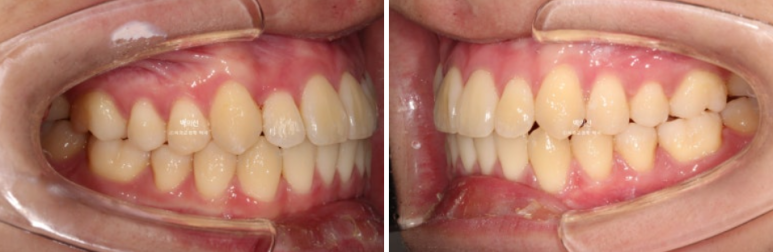

전 후 비교 보겠습니다.

24.04~25.07